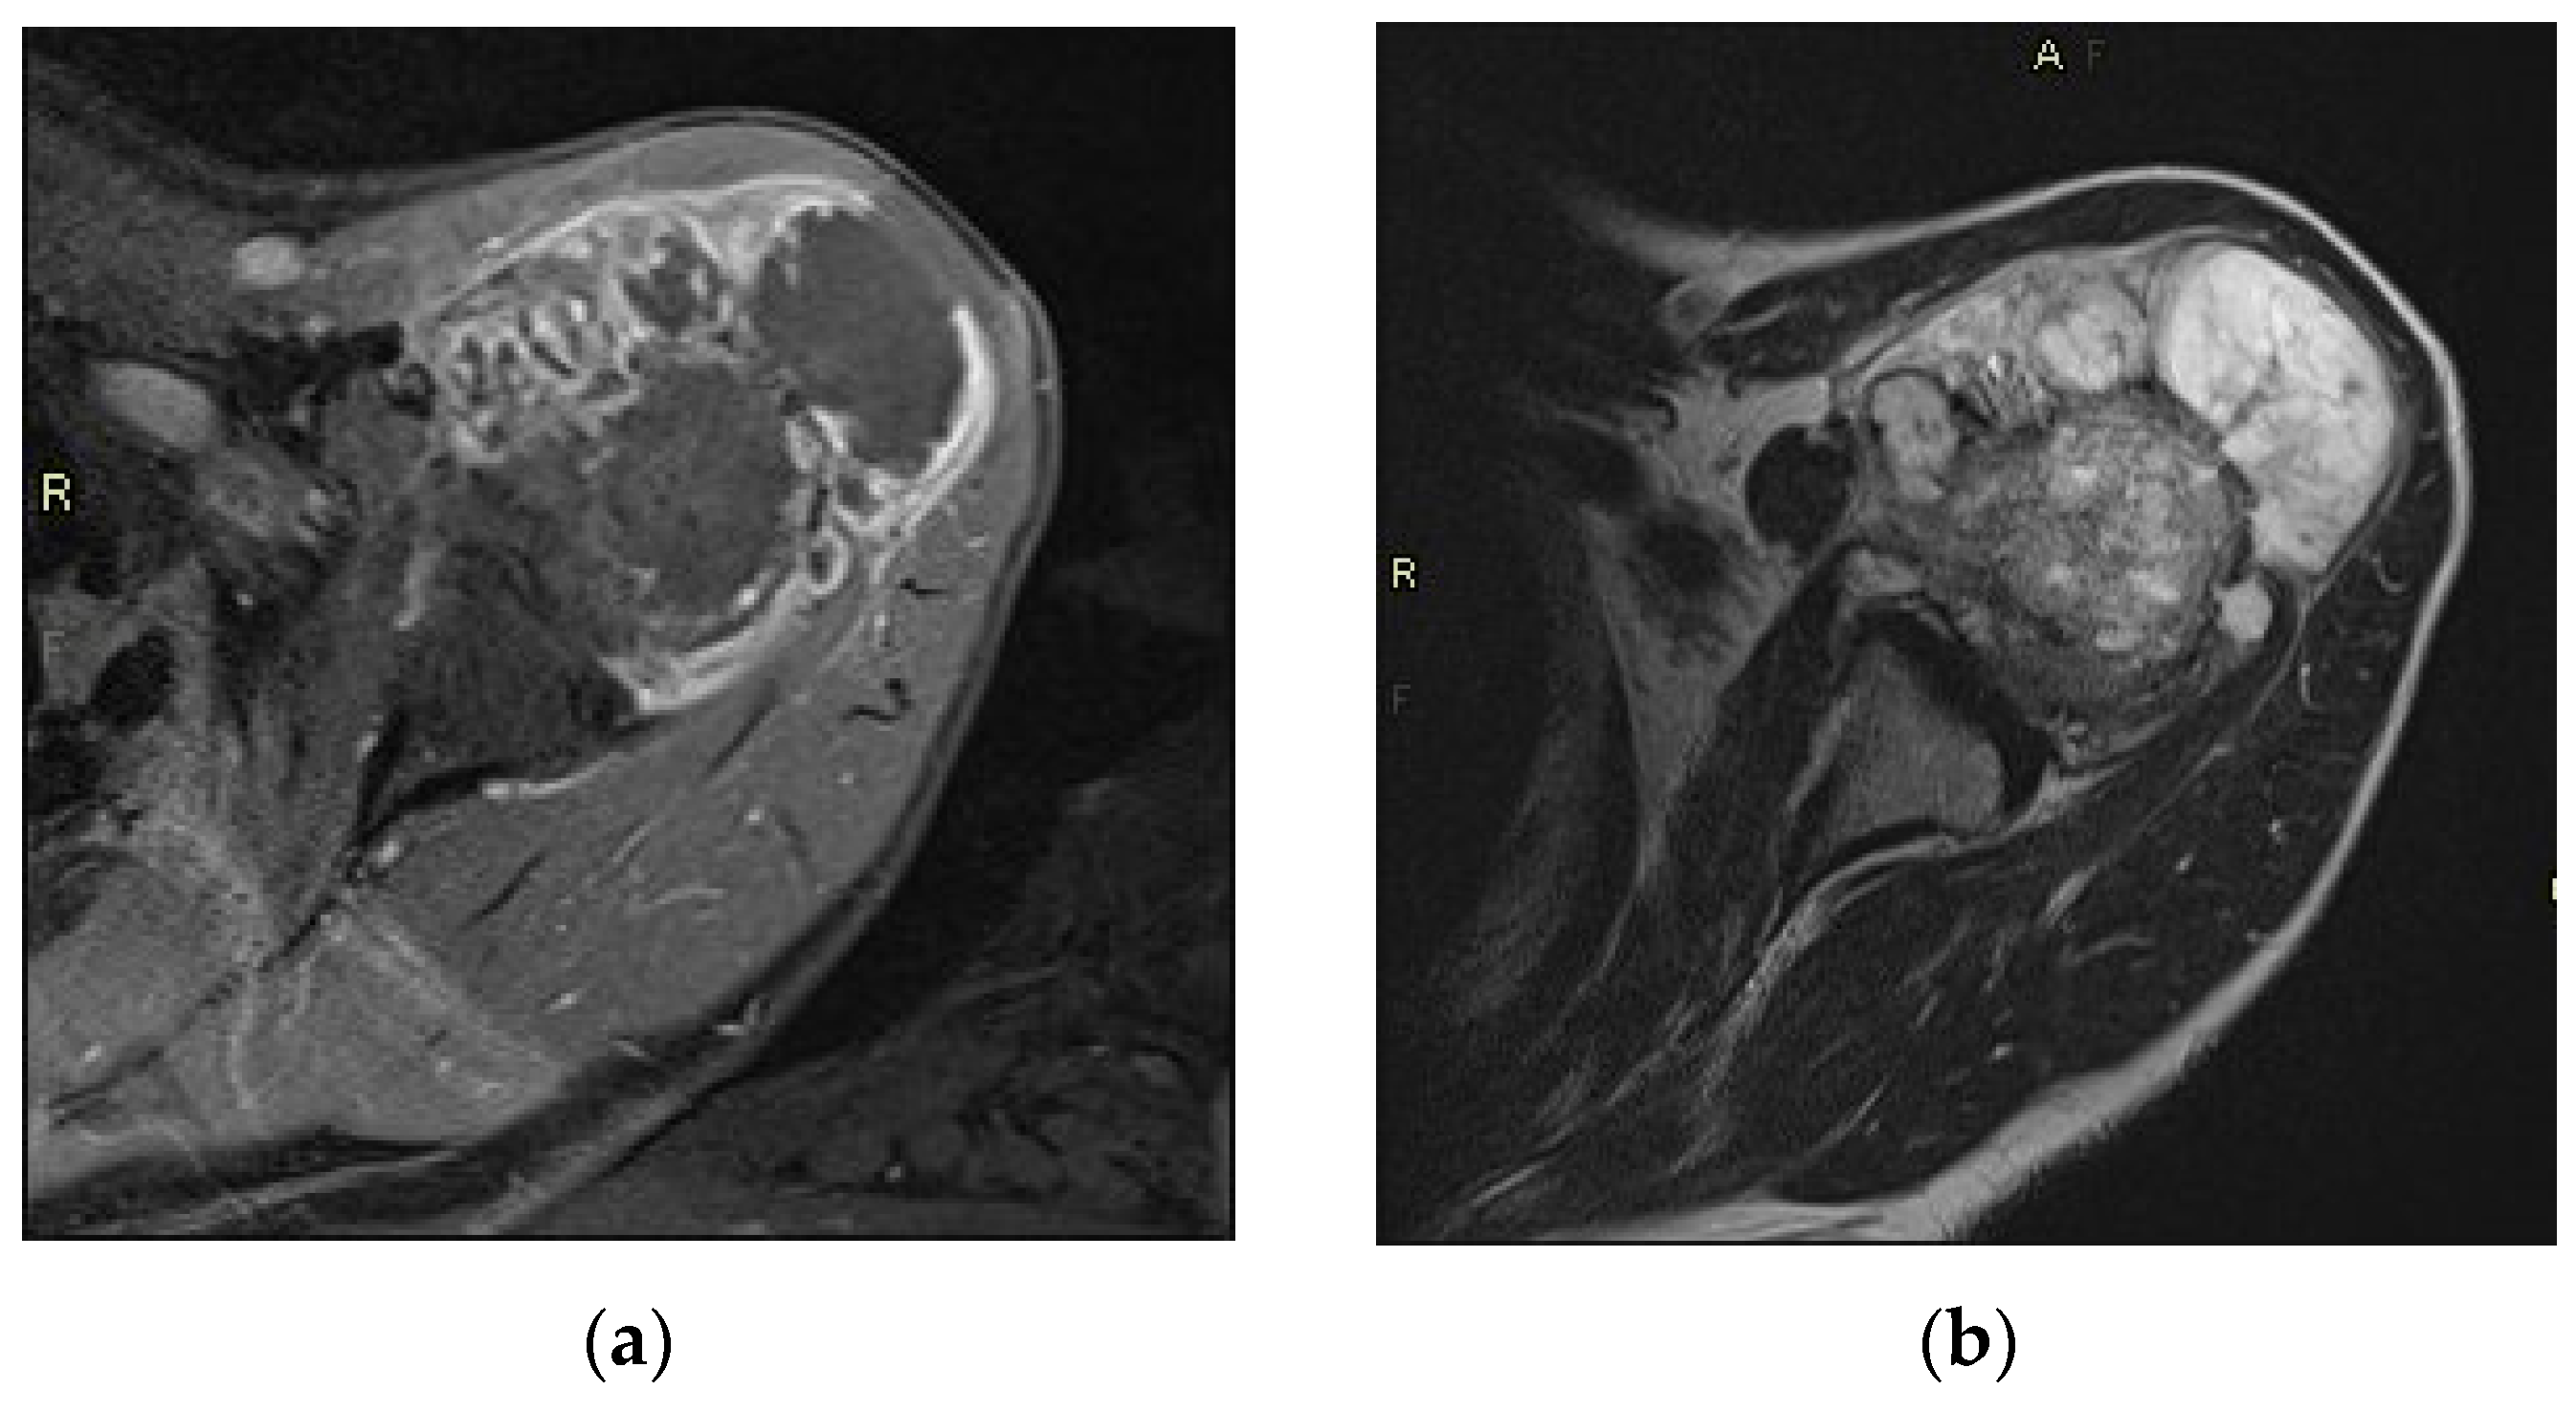

3.2. MRI Analysis